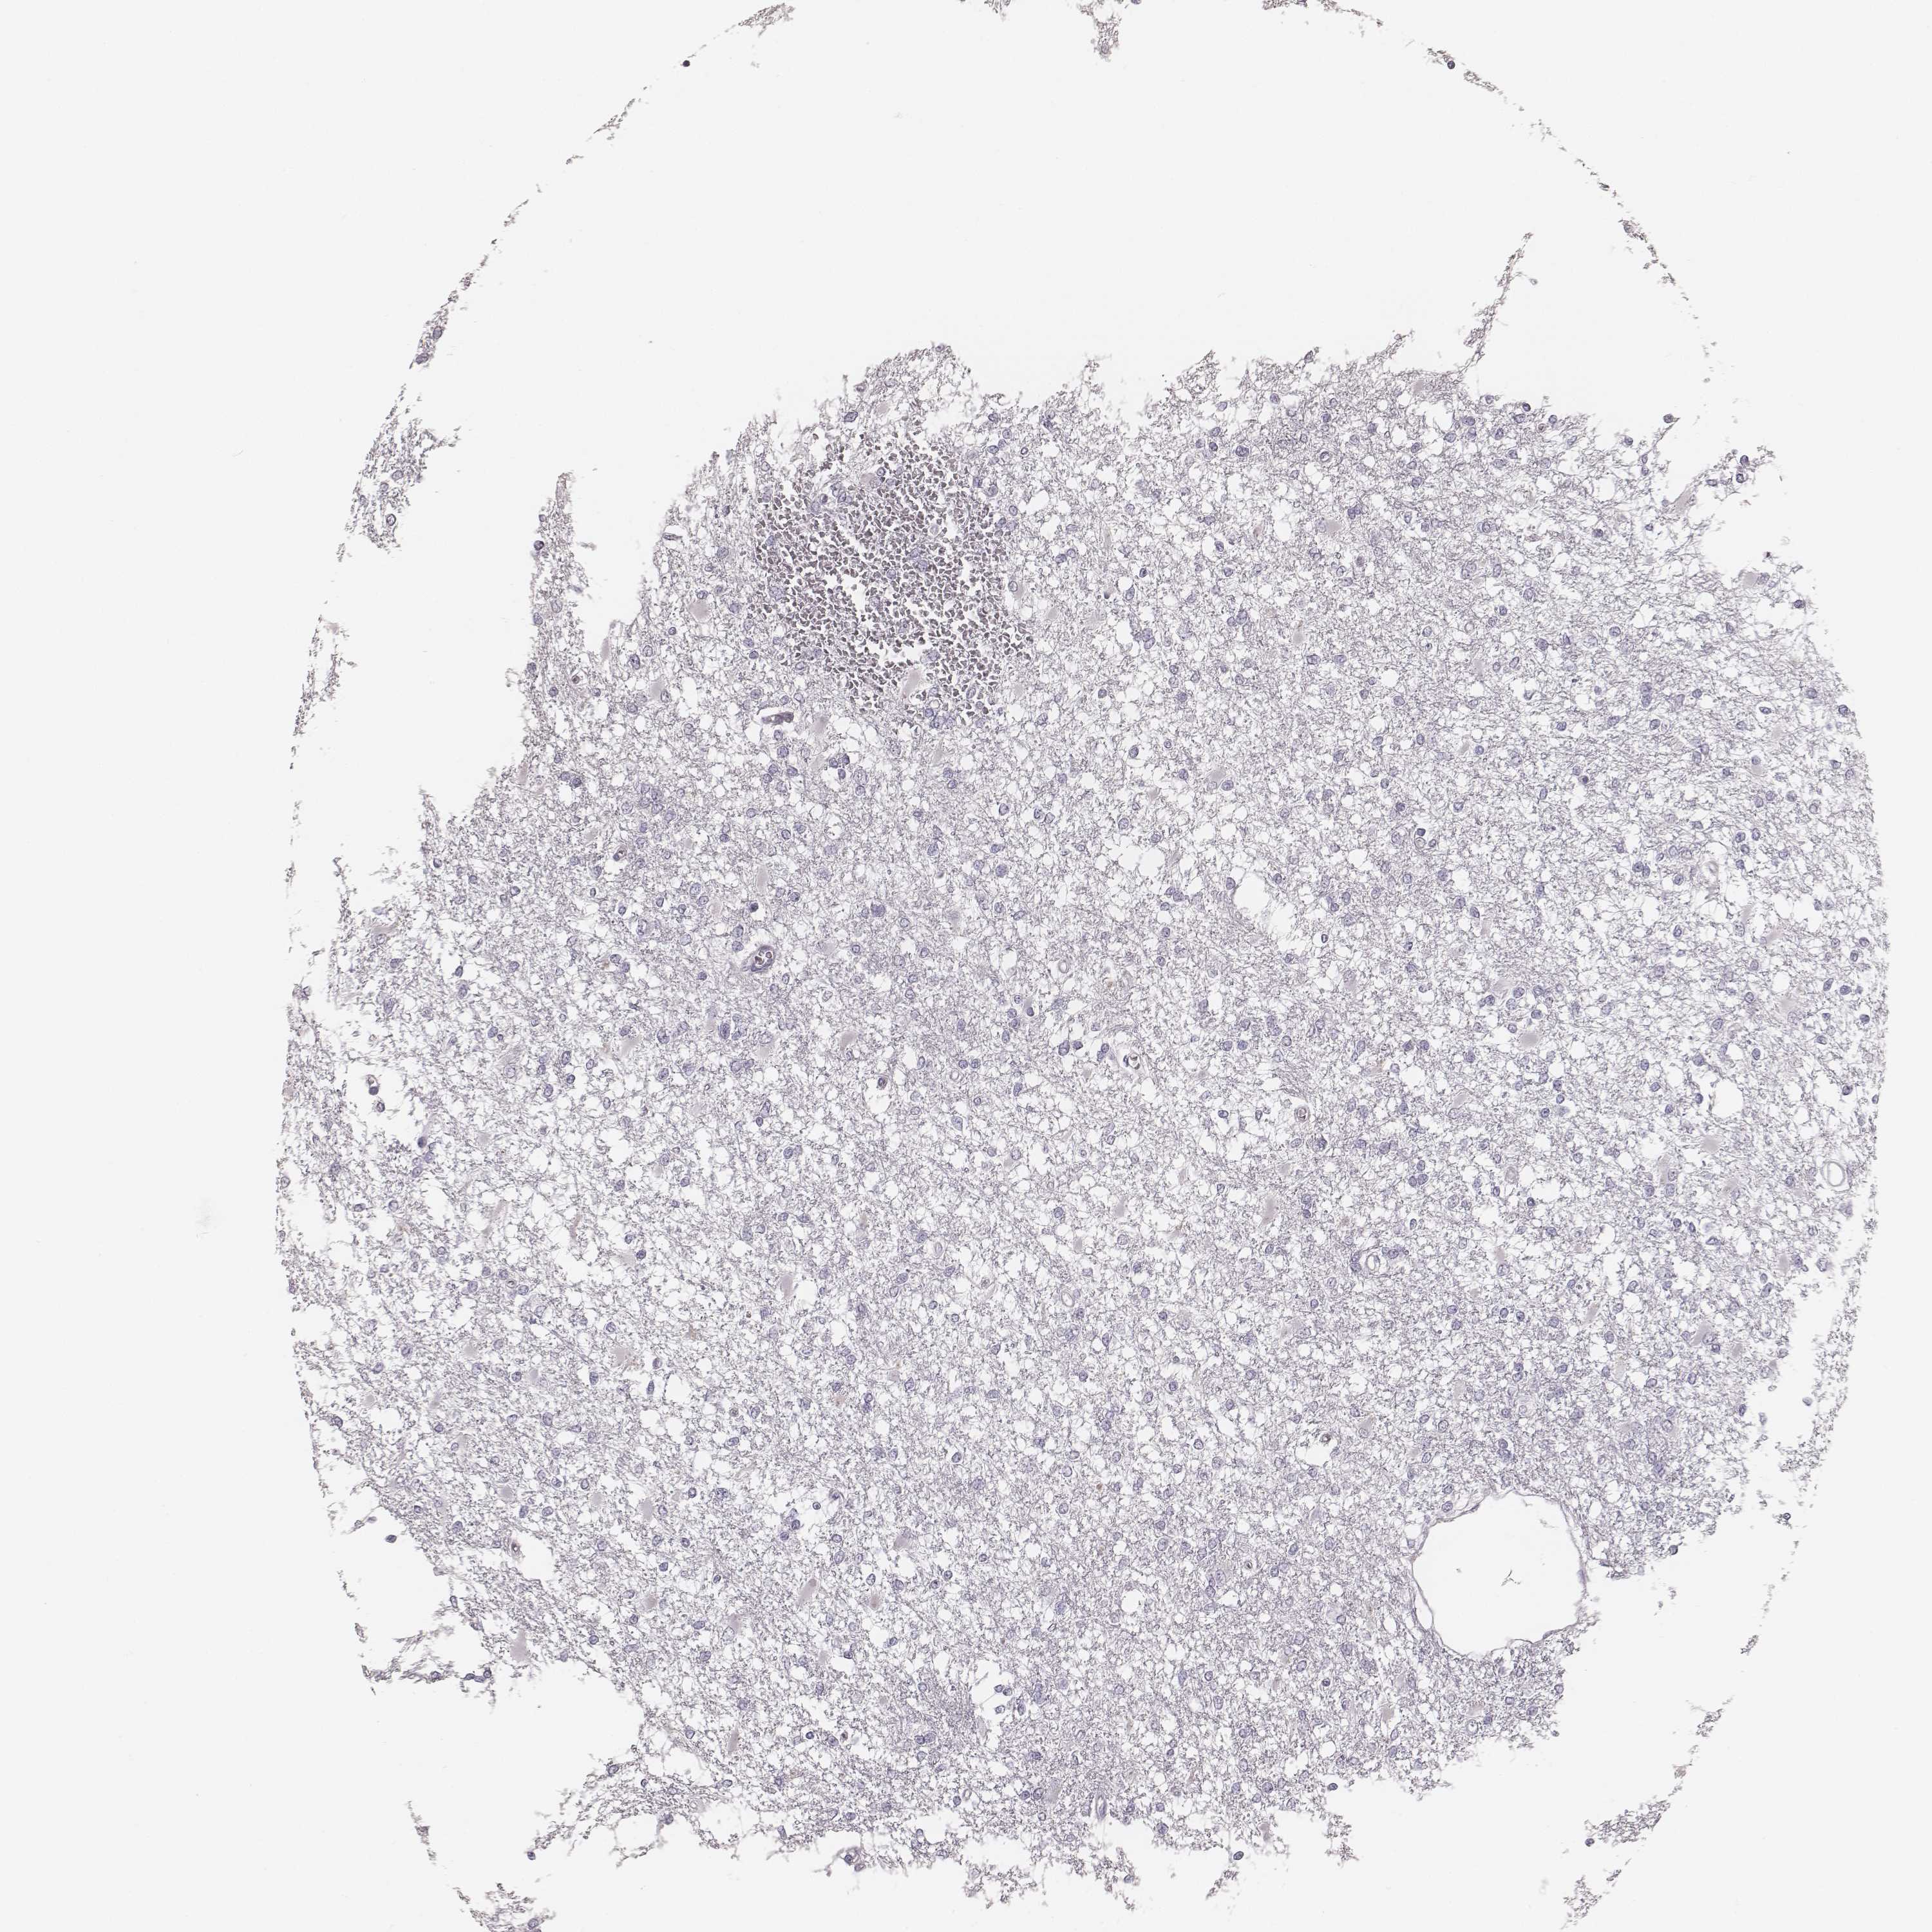

GLIOMA - Protein expressioni

A mouse-over function shows sample information and annotation data. Click on an image to view it in a full screen mode. Samples can be filtered based on level of antibody staining by selecting one or several of the following categories: high, medium, low and not detected. The assay and annotation is described here.

Note that samples used for immunohistochemistry by the Human Protein Atlas do not correspond to samples in the TCGA dataset.

Antibody stainingi

Antibody staining in the annotated cell types in the current human tissue is reported as not detected, low, medium, or high, based on conventional immunohistochemistry profiling in selected tissues. This score is based on the combination of the staining intensity and fraction of stained cells.

Each image is clickable and will lead to virtual microscopy that enables deeper exploration of all samples and also displays staining intensity scores, fraction scores and subcellular localization as well as patient and tissue information for each sample.

Antibody HPA051929

Staining

High

Medium

Low

Not detected

Intensity

Strong

Moderate

Weak

Negative

Quantity

>75%

75%-25%

<25%

None

Location

Nuclear

Cytoplasmic/membranous

Cytoplasmic/membranous,nuclear

Glioma, malignant, Low grade

Glioma, malignant, High grade

Glioma, malignant, NOS